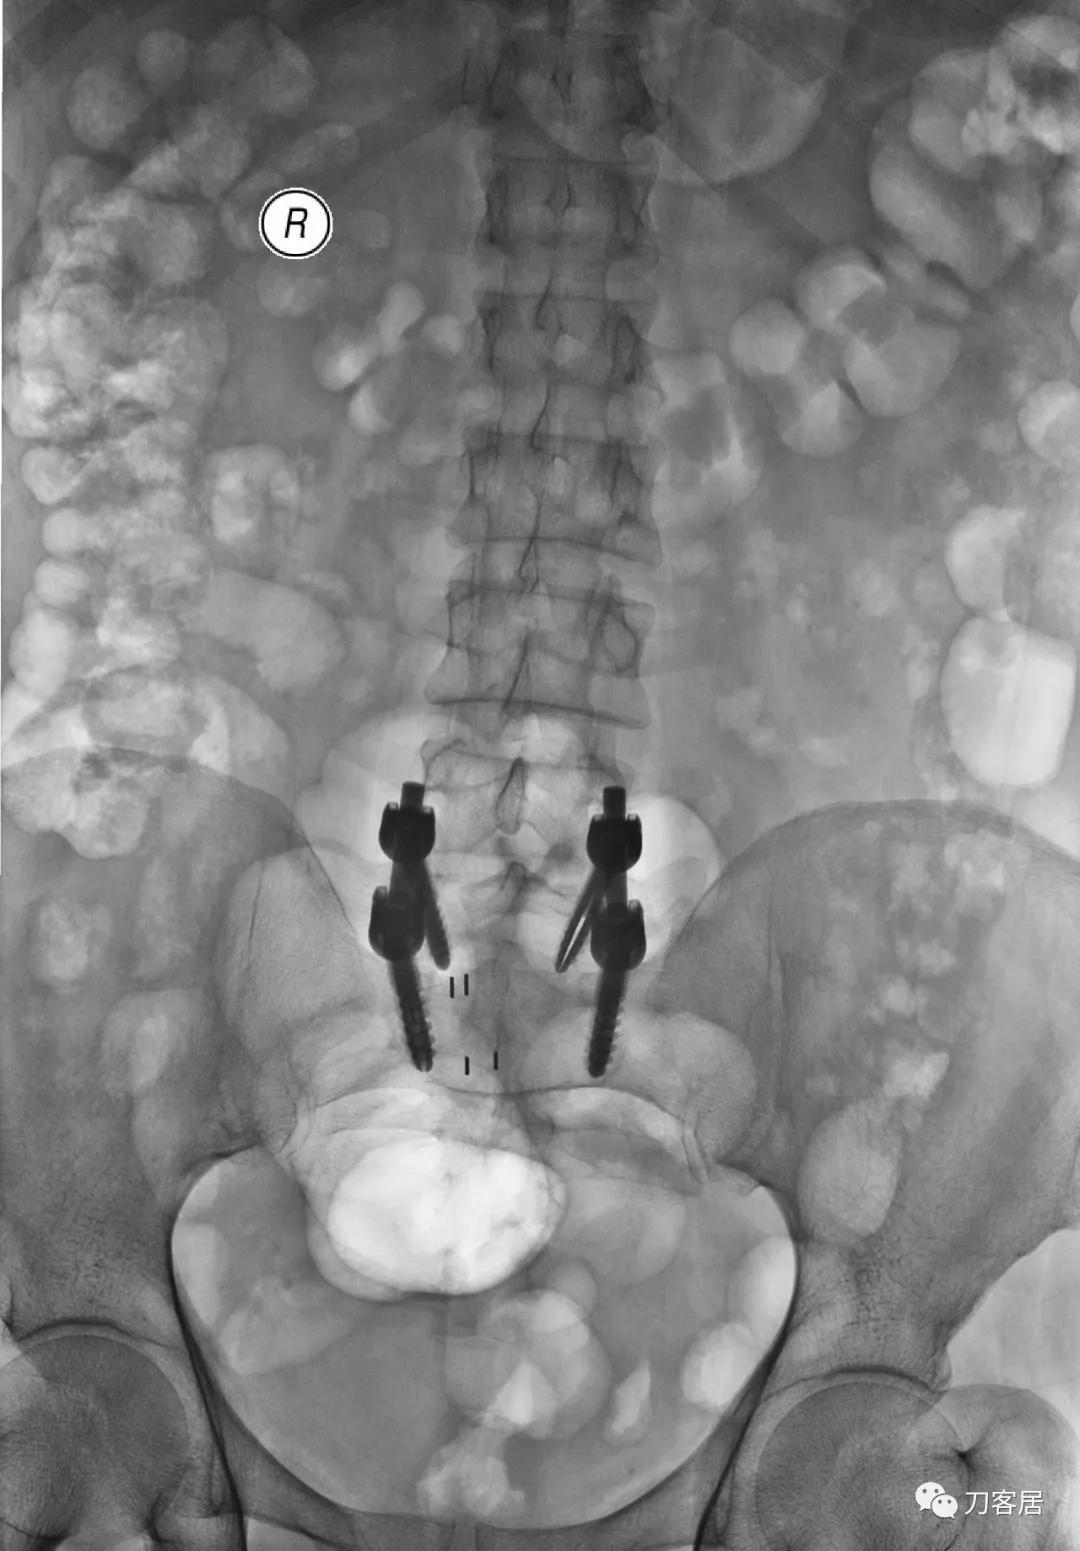

图15. 20210701术后腰椎正侧位X线片

图16. 20210701术后腰椎正位X线片

手术后原有症状缓解。患者同时有骨质疏松症,骨密度-3.1, 住院期间同时予以抗骨质疏松症治疗。高中同学反馈,患者回家后症状明显缓解,心情也好转。